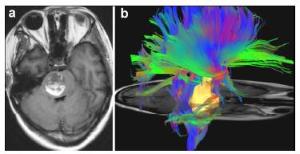

20170712151348 Figure 2 The surgical approach designed with the aid of DTI. T1-weighted (a) showed the lesion located in the right side of pontine. The three dimensional DTI (b) showed that the anterior and posterior side of the lesion was surrounded by tracts. The right approach to resect this lesion should be from the lateral side (we chose subtemporal approach).